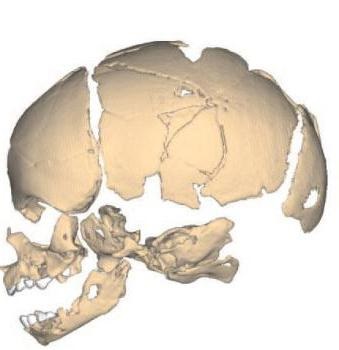

Jellemzői a szerkezet a koponya csecsemők

A csontváz egy újszülött nagyon különbözik attól, amit lehet látni a felnőtt. Skull jól fejlett többi részéhez képest a test és egy nagy kört, és az agy osztály sokkal nagyobb, mint a személyes. Azonban, a fő különbség a kettő között a jelenléte kutacsok - porcos ízületek, maradványai a hártyás koponya, amely végül helyébe csontszövet. Ezek jelenléte lehetővé teszi, hogy a csontok a fej mozog, és ezáltal azt, hogy áthaladjon a szülőcsatornán szülés közben elleni védelemmel mindenféle sérülések. Továbbá, azok a kompenzációs mechanizmus, amely megvédi az agyat a fejsérülés az élet korai szakaszában.

Nagy (elöl) kutacs - a legkiterjedtebb, található, ahol a csatolt temporális és parietális csontok a koponya, akkor zár, amikor a gyermek eléri a két évet.

Kis (hátul) kutacs között fekszik a parietális és nyakszirti csontjait, ő gyorsan felállt - már a második vagy a harmadik hónapban a gyermek fejlődését.

Vannak még kis ék és mastoid kutacsok található oldalsó felületén a koponya és megcsontosodott röviddel a születés után.